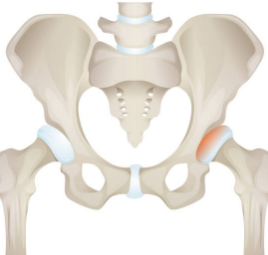

대퇴골두 무혈성 괴사

대퇴골두로의 혈액 공급이 차단되어 뼈 조직이 괴사하는 경우, 인공관절 치환술이 필요할 수 있습니다.